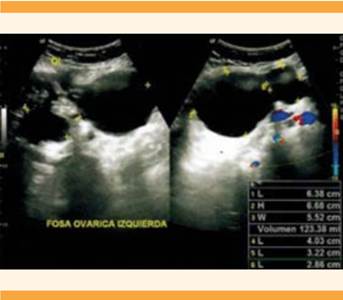

Los marcadores tumorales CA-125, CA 19-9 y el antígeno carcinoembrionario se determinaron en valores normales. El rastreo ultrasonográfico encontró, en la fosa ovárica izquierda, una imagen quística simple, con paredes ecogénicas definidas de 123 cc; otra imagen quística compleja, de menor tamaño, a expensas de septos gruesos de aspecto multilocular, con interior heterogéneo predominantemente anecoico, con ecos finos en su interior (volumen de 18 cc) y un componente sólido ecogénico de 25 x 20 mm.